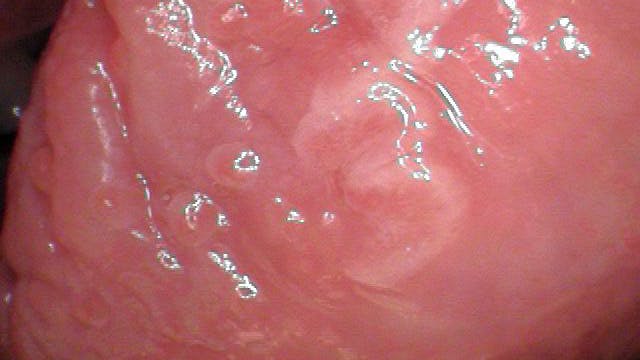

Clinical assessment revealed a 6 mm x 8 mm white leukoplakic lesion on the left lateral border of the tongue. The lesion was not painful to palpation or touch, and it was slightly corrugated with irregular borders.

Acute glossitis with superficial erosions superimposed on pseudoepitheliomatous squamous hyperplasia with mild atypia

The unknown etiology of the lesion automatically put it into a category that made it a high-risk leukoplakia, especially since it had been present for just under a year. The patient was referred to an oral surgeon for excisional biopsy. The final diagnosis, as given above, did not reveal any evidence of malignancy. Because the findings were consistent with inflammatory changes, it was recommended that the patient be monitored for any future premalignant changes or tendencies. A three-month follow-up was recommended.